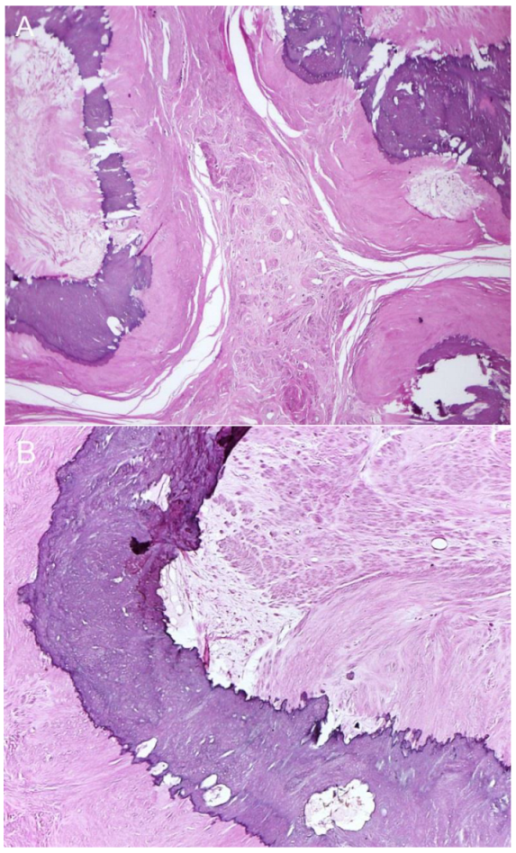

Figure 4. Operative findings and pathological examination confirmed a severely calcified uterine leiomyoma. The mass was well demarcated and composed of multiple nodules of collagen-rich smooth muscle tissue, which contained frequent central islands or irregular ring-like bands of calcifications. The smooth muscle cells were arranged in interlacing fascicles and showed bland and uniform nuclei, without atypia or increased mitotic activity. Microscopic pathology: (A) Collagen-rich nodules of smooth muscle tissue containing calcifications in the central zone. (B) Interlacing fascicles of smooth muscle cells without nuclear atypia adjacent to the calcification band.